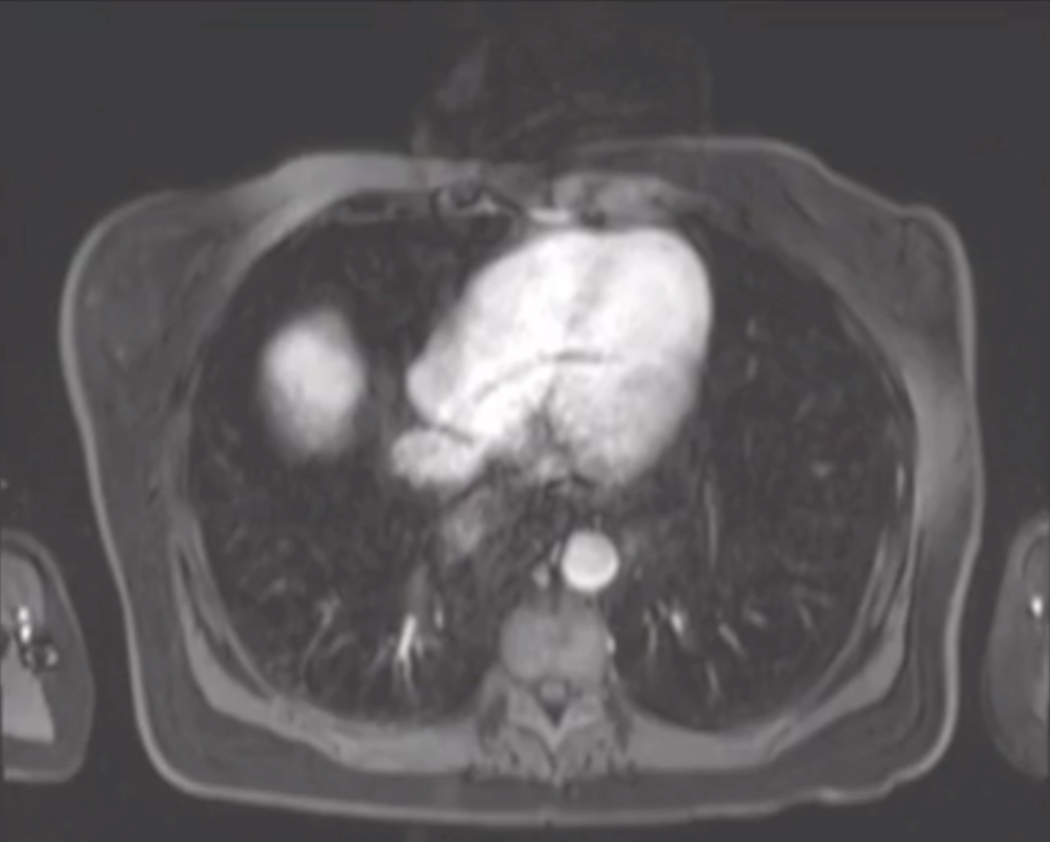

Pulsation artifact

• Occurs in phase encoding direction

• Takes longer so done in shorter axis

• In chest MR = AP

• In breast MR = side to side

• Even though sided to side is wider and therefore will take longer you cannot have artifact in front of the chest in the breast tissue